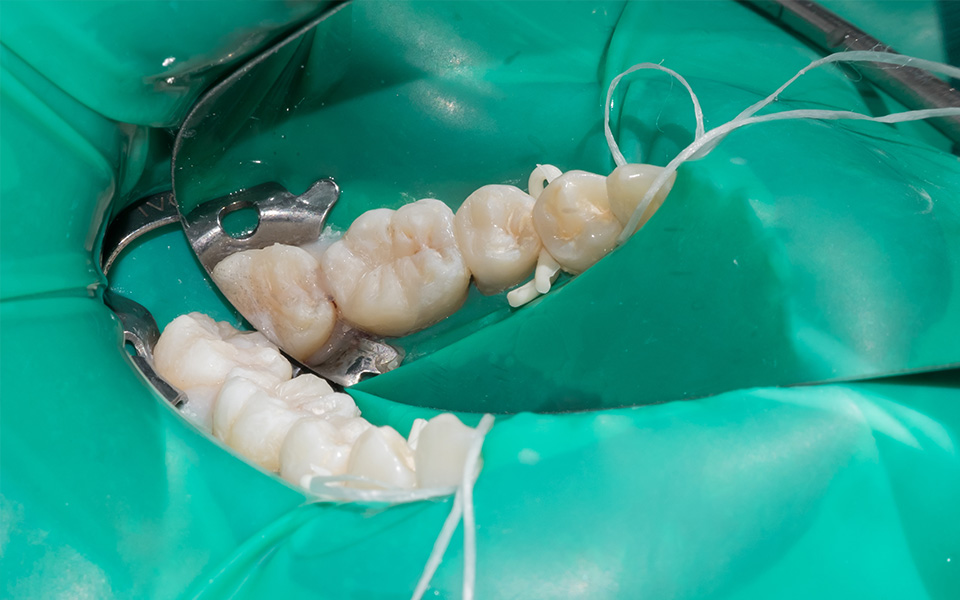

口腔内にはさまざまな細菌が存在し、根管治療中に唾液を介して内部に入ってしまうと、再発のリスクは50%まで高まると言われています。このリスクを回避するために、当院では、根管治療など神経の治療時には「ラバーダム」というゴムシートを使用しております。ラバーダムを装着すれば、再発のリスクは10%以下まで下げることができます。また、治療中(特に奥歯の治療)は舌や頬が邪魔になり、治療がしにくい場合がありますが、ラバーダムを装着することで歯だけを露出させることができ、根管治療の精度を高めることから、ラバーダムは根管治療では必須器具となります。

| 治療内容 | ラバーダムを用いて無菌的な環境下で再治療(過去に根管治療をしている歯の治療)を行いました。 過去に詰めた修復物の周りが虫歯になってしまっていたため、マイクロスコープ下で虫歯を完全に取り切り、 NiTiファイルを用いた根管形成、薬液や超音波器具による洗浄、体に馴染みの良い材質による充填、被せ物を支え、再感染しないように土台を立てました。 |

| 治療内容 | ラバーダムを用いて無菌的な環境下で根管治療を行いました。 マイクロスコープ下で虫歯を完全に取り切り、根の管の細さが0.06mm程度になっていたため慎重にNiTiファイルを用いて根管形成を行い、 薬液や超音波器具による洗浄、体に馴染みの良い材質による充填、被せ物を支え、再感染しないように土台を立てました。 |

| 治療内容 | ラバーダムを用いて無菌的な環境下で根管治療を行いました。 マイクロスコープ下で虫歯を完全に取り切り、NiTiファイルを用いた根管形成、薬液や超音波器具による洗浄、その後根管内をさらに消毒するため水酸化カルシウムを入れて仮の蓋をしました。 2回目は体に馴染みの良い材質による充填、被せ物を支え、再感染しないように土台を立てました。 |